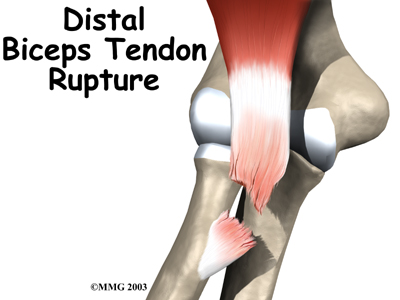

Surgical procedure to reattach tendon. My 'S' shape incision was only 2". Just over half of this patient.

Xray of titanium anchor just below elbow. Center: overhead view - looking down

Final results at right (bicep belongs to Charles Atlas)